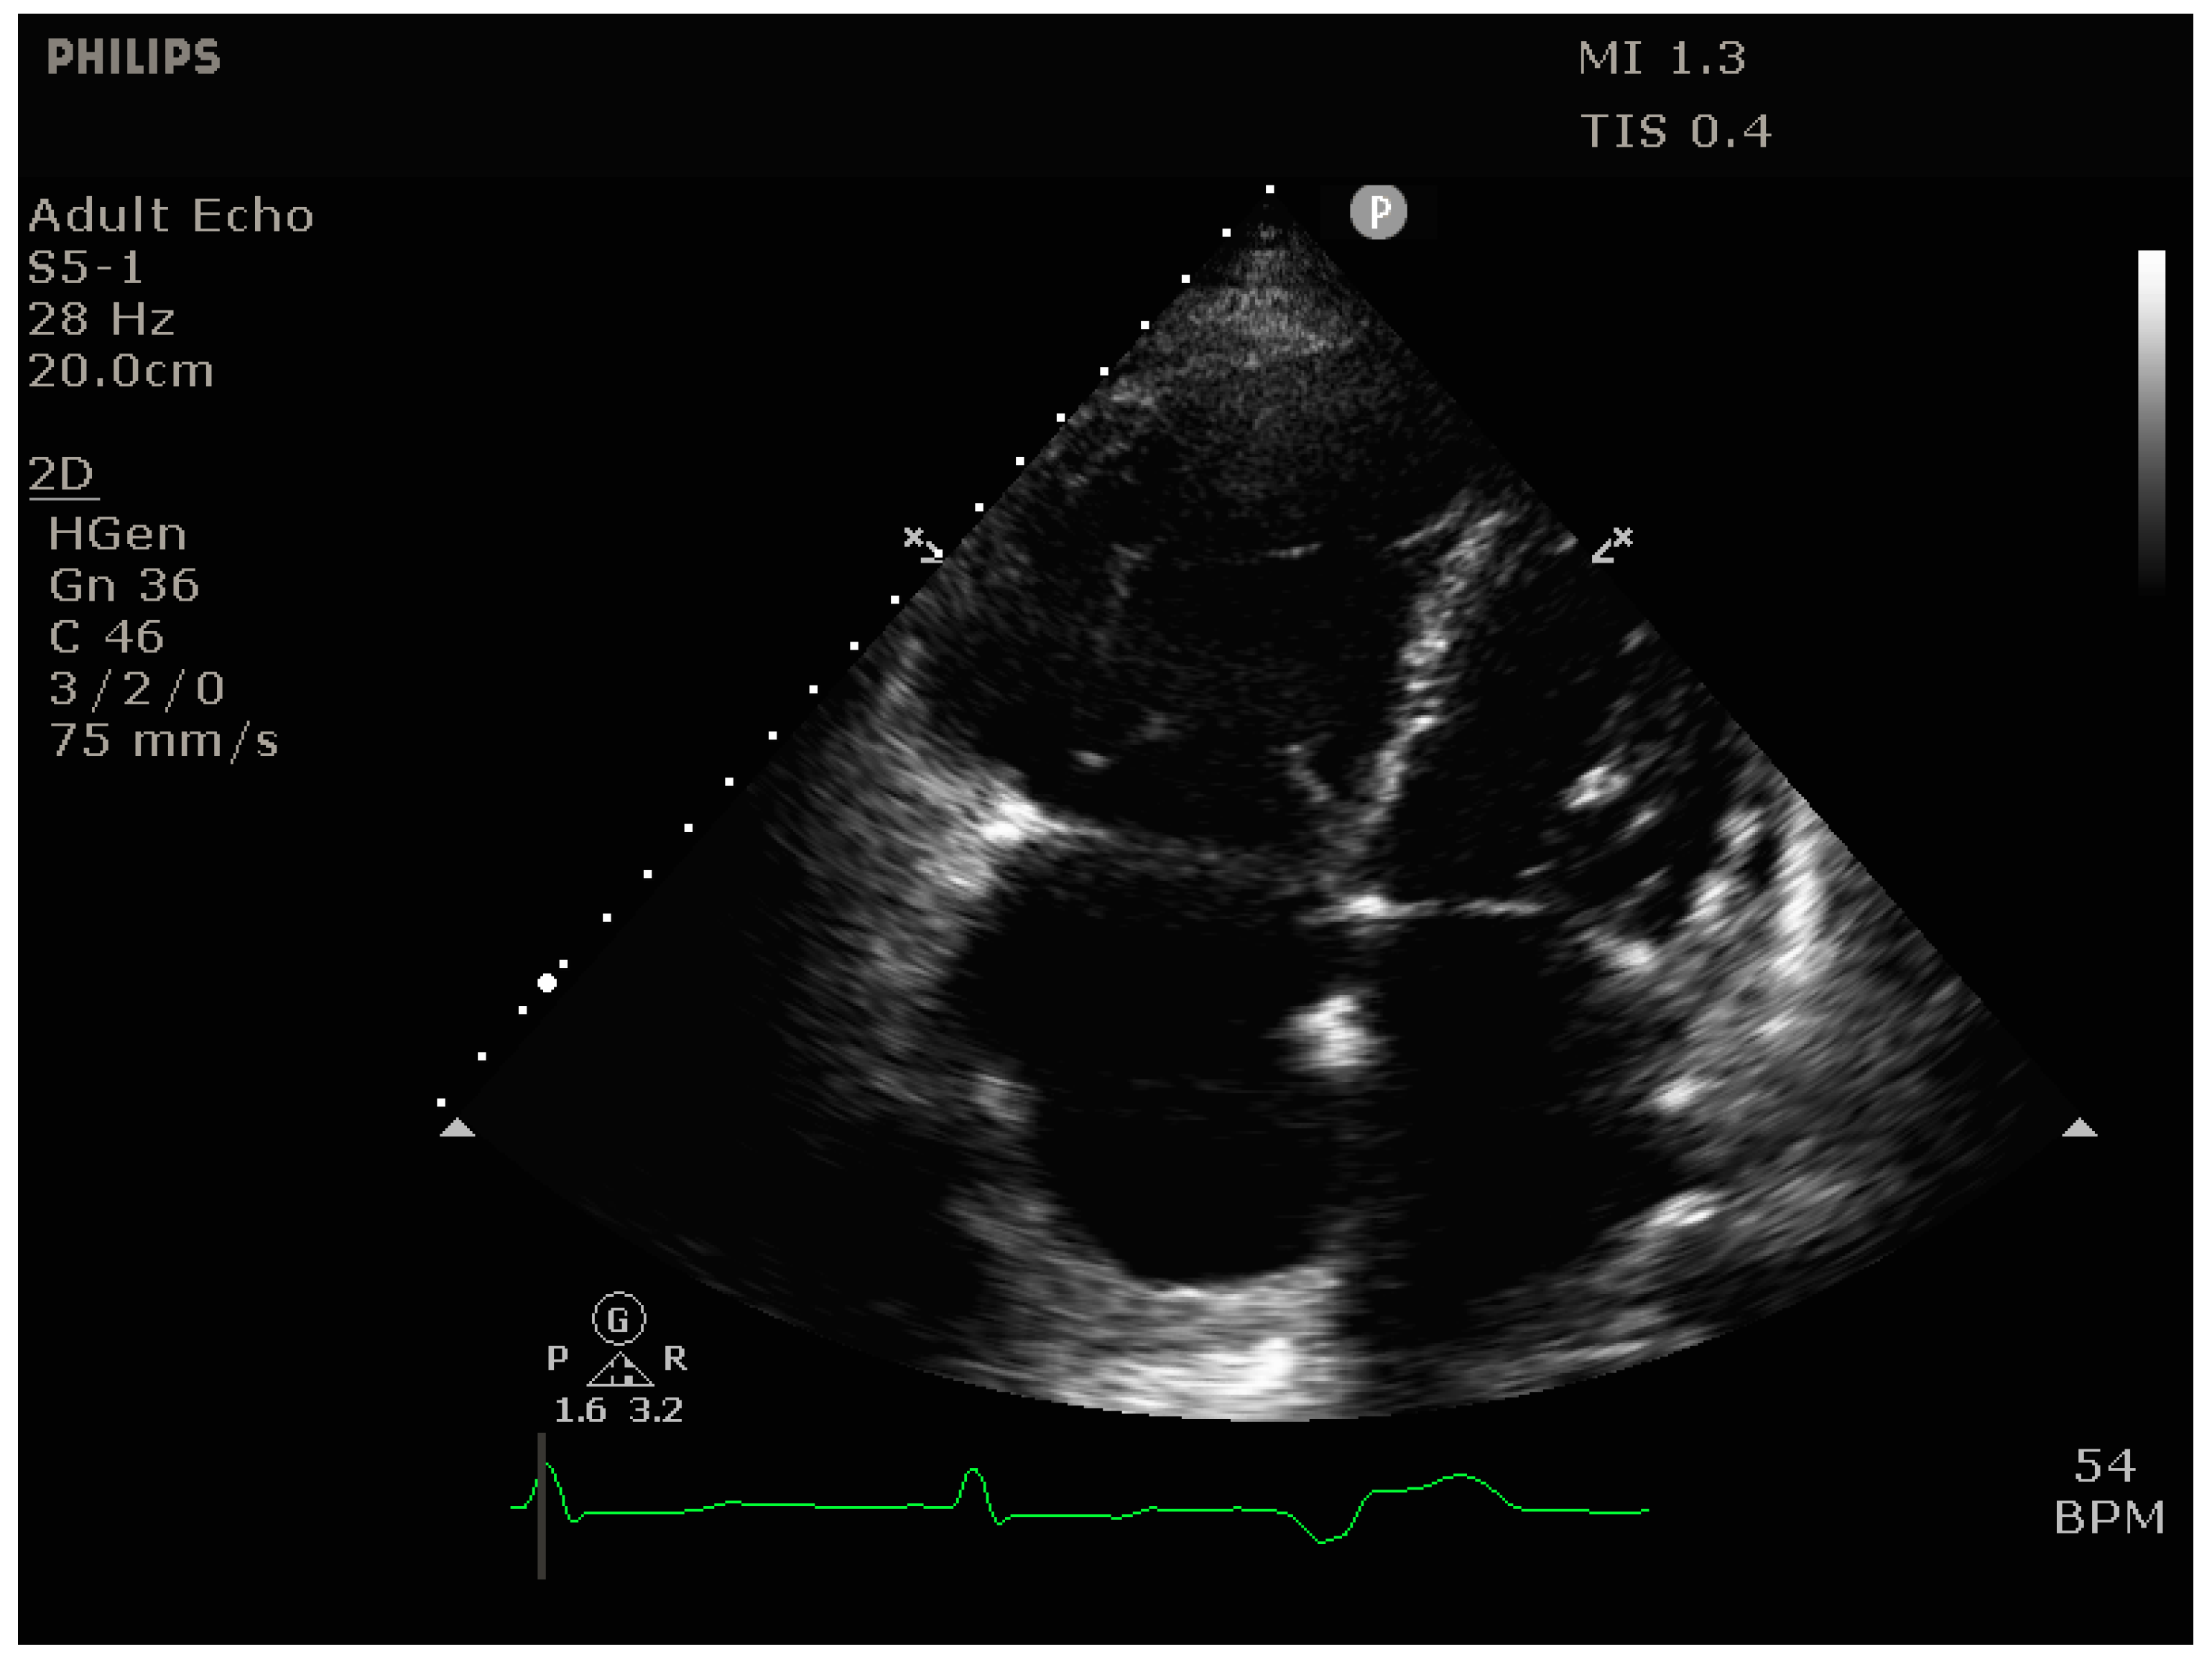

Identify this view.

RV modified apical 4C.